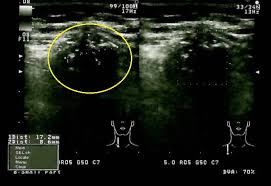

Helminth Malaria Co Infection Papillary Thyroid Cancer Ncbi

Helminth Malaria Co Infection Papillary Thyroid Cancer Ncbi Source from : http://bebe-strumf.ro/605-helminth-malaria-co-infection.php